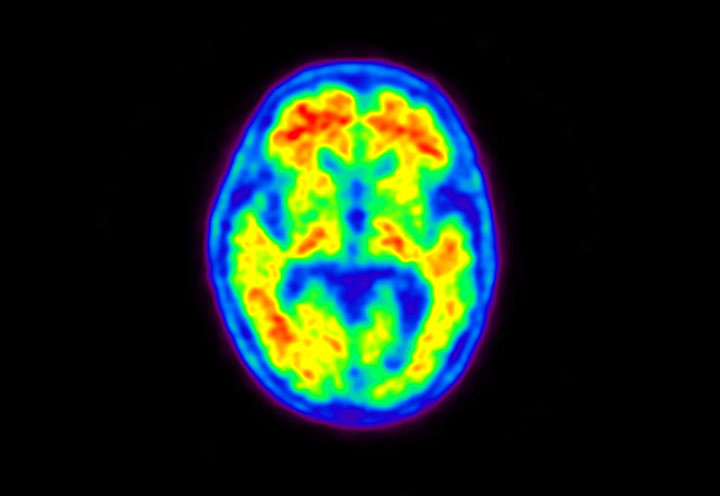

Head / Case5 : Amyloid

Courtesy : Kindai University Hospital

- Imaging protocol

- Injected dose: 4.27 MBq/kg, 18F-Flutemetamol

- Uptake time: 99 minutes

- Scan time: 20 minutes